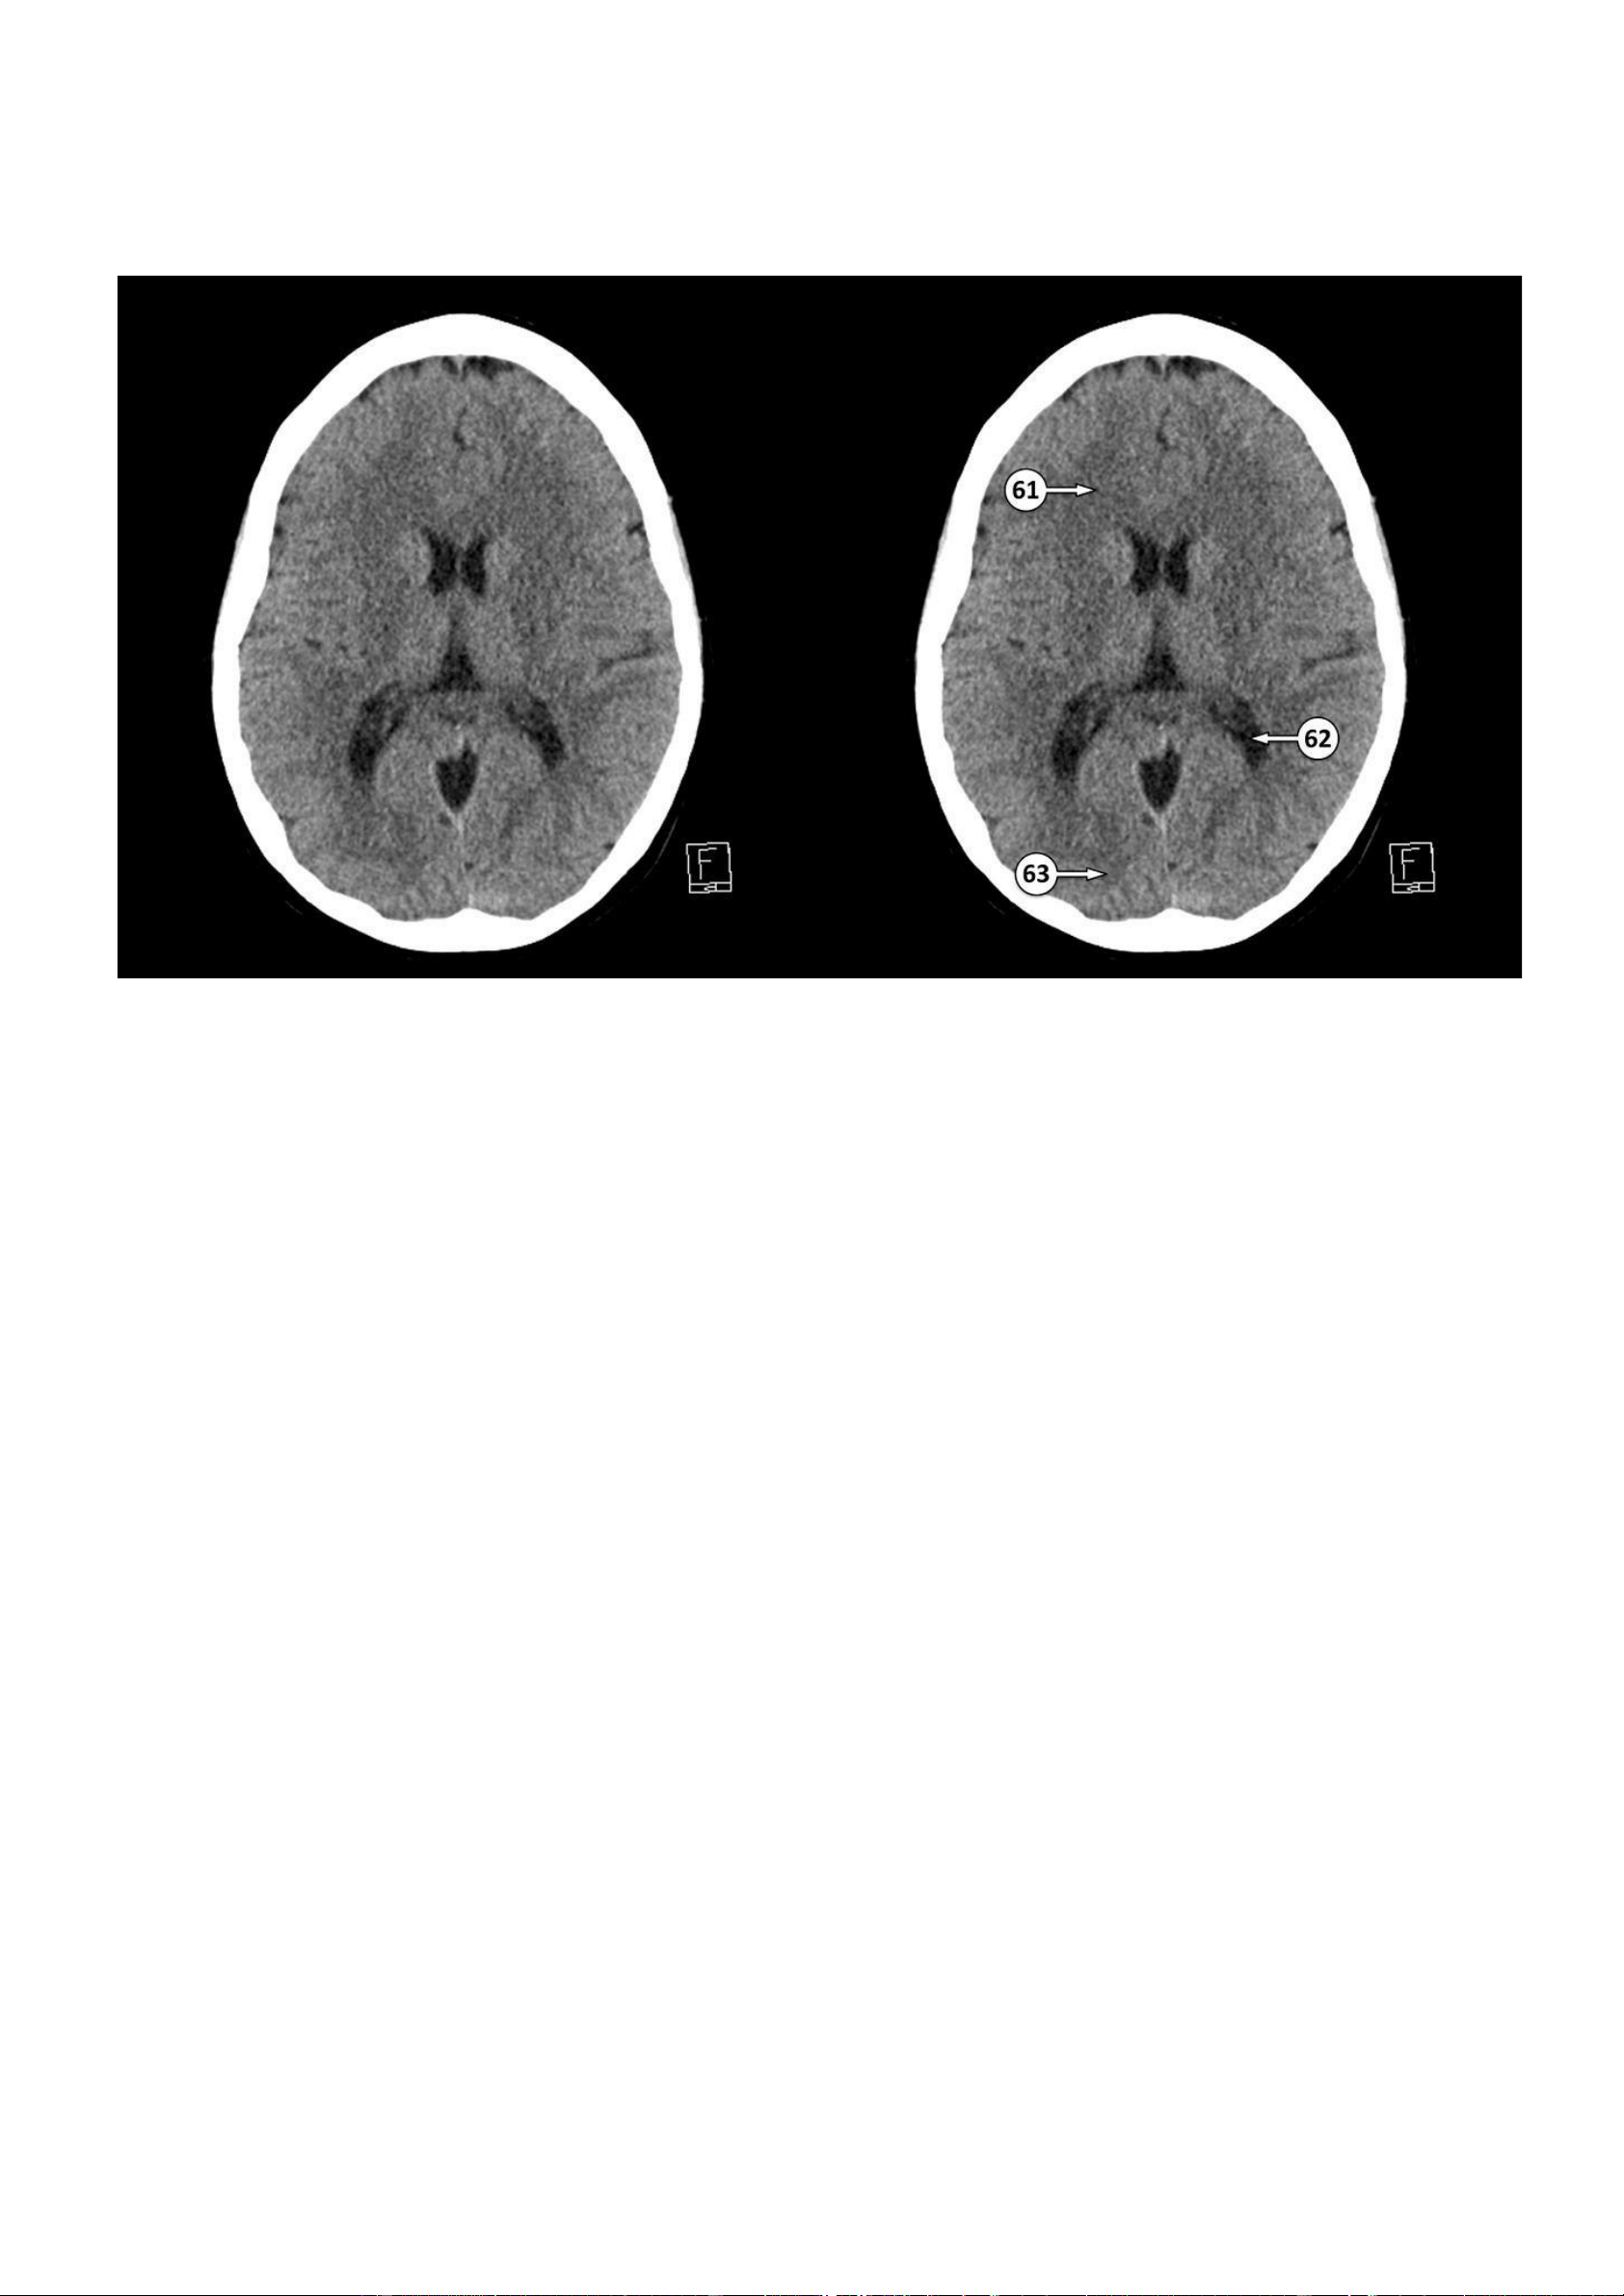

Thảo Thảo & Bé Nghìn Dặm 59: Vách trong suốt 60: Đồi thị ▪ Số 61: Bó nhỏ

▪ Số 62: Hợp lưu sừng chẩm và sừng thái dương của não thất bên ▪ Số 63: Thuỳ chẩm lOMoAR cPSD| 22014077